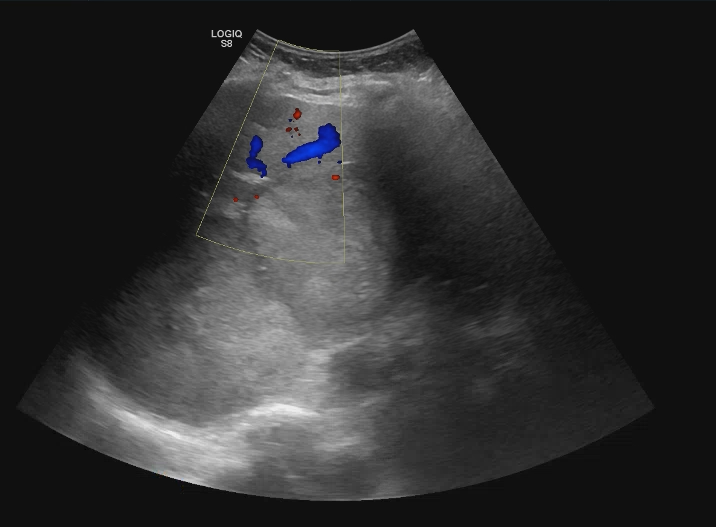

Se realiza ecografía abdominal en la consulta que muestra abundantes lesiones ocupantes de espacio en ambos lóbulos hepáticos, alguna de gran tamaño.Otras pruebas complementarias realizadas (si existen)

Hígado con múltiples metástasis y ambos lóbulos, la más gruesa de uns 10,2 cm en los segmentos VI y VII. Colecistolitiasis. Vía biliar no dilatada.Esplenomegalia con nódulos 12 y 14 mm inespecíficos. Nódulos suprarrenal izquierdo de 46 mm y dos derechos de 14 y 18 mm, inespecificos. Páncreas de medida y morfología normal. No hay signos de uropatía obstructiva. Riñones dentro de la normalidad con el nefrograma simétrico. Adenopatías retroperitoneales de predominio retrocavales y enteraortocava, la mas gruesa de 19 mm. Lesiones líticas en las costillas, esternón, vertrebrales y pelvianas. Conclusión: Enfemerdad neoplasia con diseminacion pulmonar y hepática, osea, ganglionar y probablemente esplenica y suprarrenal bilateral. No se identifica origen.

Biopsia de nódulo hepático positiva para melanoma maligno.